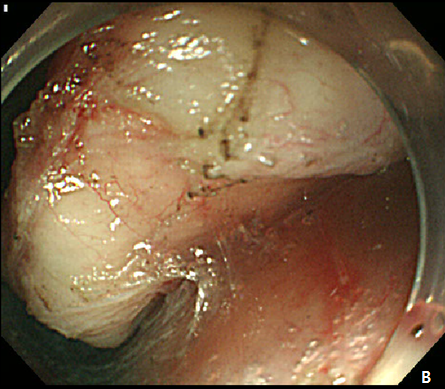

Figure 2 Endoscopic submucosal dissection (ESD) of esophageal subepithelial tumor (SET).

(A) At initial,an incision was made from the regular mucosal layer. (B, C) Esopahgeal SET was successfully resected by using conventional ESD method. (D) A large muocsal defect was noted after the procedure.